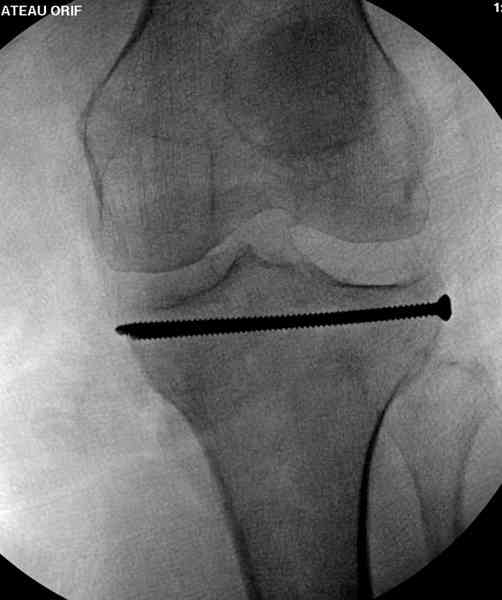

Из медиального окна можно приподнять латеральную

импрессию. Фиксация тремя параллельными шурупами в

эпифизарной части над импрессией. Создается крыша,

которая предупредит коллапс. На образовавшуюся полость - костная пластика из аутокости или синтетический заменитель. Мы применяем Osteoset в 4-5 мм диаметре таблеточки или иньекционную форму Prodens.

Нет, малоберцовый внизу, фиксацию проводим на верхнем эпифизе, где твердая кость. Задача состоит

в том, чтобы создать арматуру из нескольких проведенных шурупов на эпифизе.

Это техника применяется, когда имеется

центральная импрессия, а при ипрессии с краевым переломом - после приподнимания импрессии опорная (Butress) пластина, как на снимке.